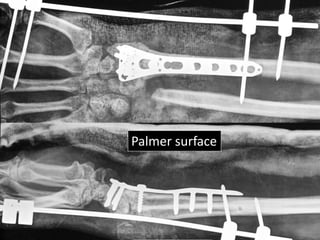

Severe Palmer flexion and ulnar deviation deformity

Dorsal

Palmer/voral

Ulnar Radial

Palmer surface

Surgery

• Volar exposure

• Removal of scar tissue and clearing of bone

ends.

• Release of soft tissue contractures.

• Shortening of ulna and plating.

• Plating of radius with bone grafting.